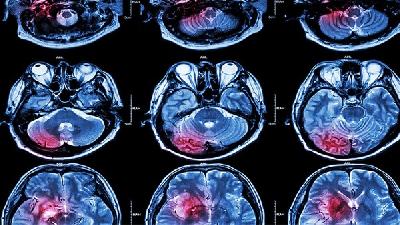

小儿脑瘫可能由遗传因素、产前感染、围产期窒息、早产低体重等原因引起,可通过康复训练、药物治疗、手术治疗等方式干预...